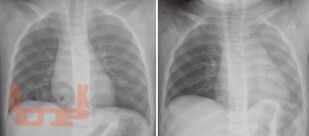

Covering various aspects of respiratory diseases in children. Multiauthored book, extensively updated by experts. Provides the key details of anatomy and applied physiology. The section on investigations has been expanded to include advanced lab investigations, pulmonary functions, and molecular tests. Common as well as rare infections, include COVID-19 infection have been covered in the section on respiratory infections. The section on noninfectious diseases covers various aspects of asthma, sarcoidosis, eosinophilic lung diseases, hydrocarbon aspirations, central hypoventilation, pulmonary hemorrhage, etc. The emerging illnesses such as primary ciliary dyskinesia, cystic fibrosis, interstitial lung diseases, etc. described in detail. These will be useful for India and other resource-limited countries. The section on acute pulmonary care including acute lung injury, mechanical ventilation monitoring and airway clearance technique that may be of immense help to practicing pediatricians who provide care for pediatric respiratory illnesses. Surgical issues that are essential for pediatricians including foreign body aspirations, intrathoracic tumors and malformations have been included. There are chapters on genetics of lung diseases, sudden infant deaths syndrome, drug and environmental diseases of lung.